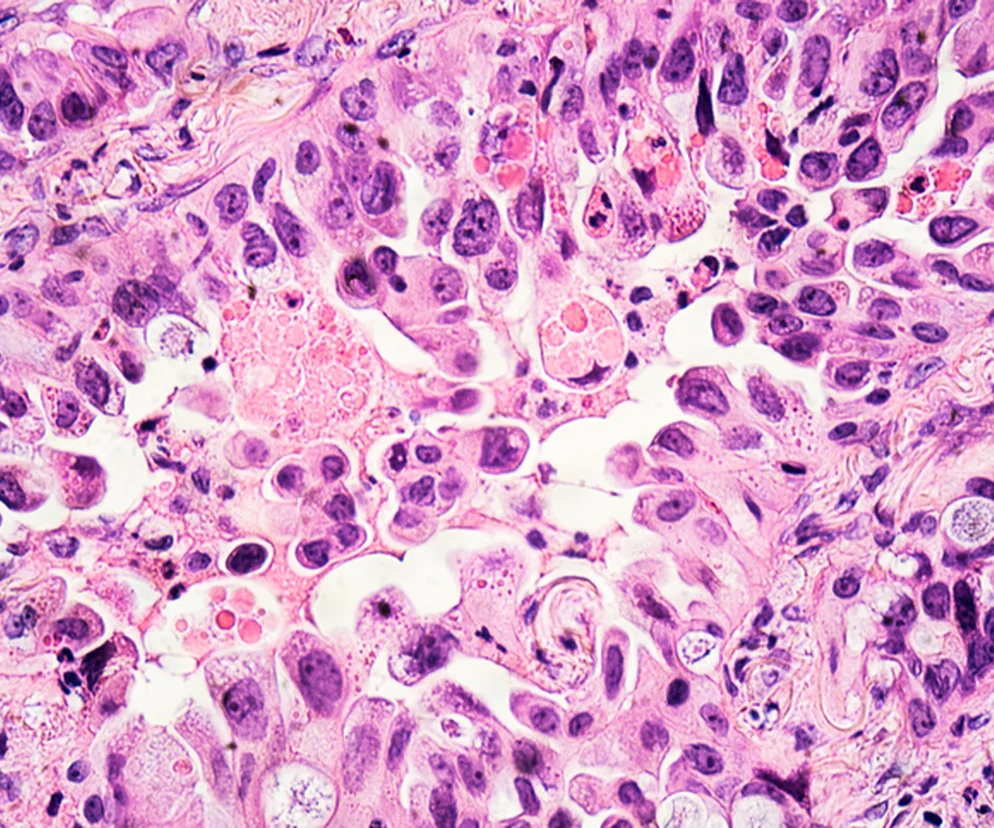

Do pewnego rozpoznania gruczolakoraka konieczne jest więc ocena tkanki nowotworu pod mikroskopem, czyli badanie histopatologiczne. Materiał do badania może zostać uzyskany podczas biopsji, czyli pobrania fragmentu tkanki nowotworowej do badania, lub podczas zabiegu operacyjnego usunięcia nowotworu. Częściej jednak korzysta się z pierwszej możliwości - wcześniejsze badanie histopatologiczne daje wiele cennych informacji, przydatnych przy planowaniu leczenia.